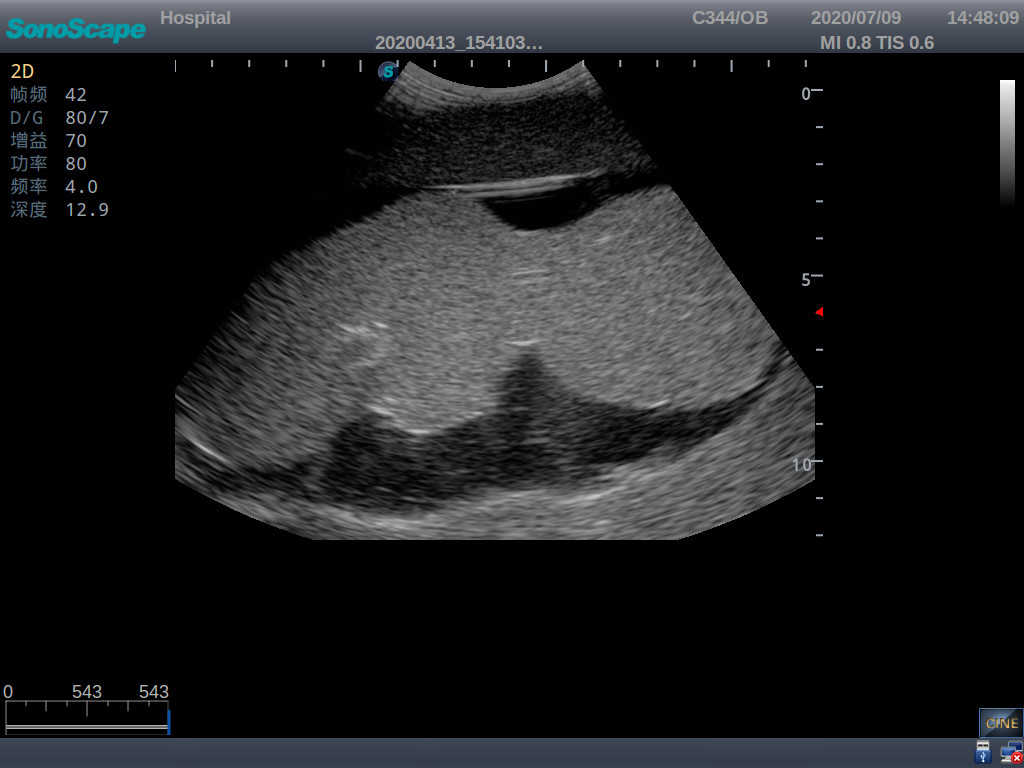

Amniocentesis Ultrasound Trainer

Model TYE1563

Outline

The trainer is designed for users to develop, practice, and validate skills associated with ultrasound guided amniocentesis procedures. With superb realism and ultra-durable design, this product is a good choice for training amniocentesis skills.

Skills Gained

· Proper transducer positioning

· Ultrasound image interpretation

· Psychomotor skills for amniocentesis

Features

· Anatomy: accurate anatomical structures and landmarks like breasts, bulged belly, fetus and symphysis pubis etc.

· Durable material with realistic feel and touch

· High-quality ultrasound images for users to recognize 22-week fetus, placenta, placenta, umbilical cord and amniotic fluid

· Self-healing material for repeated punctures

· Compatible with various real ultrasound machines

· Adjustable amount of amniotic fluid to meet different training needs

· Realistic sense of breakthrough when puncturing the amnion cavity and amniotic fluid can be drawn out